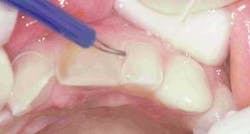

Preparation of the four incisors was then initiated using diamond burs from the Shofu Contemporary Cutting Kit (Figure 5). With the high-speed ElectroTorque KaVo handpiece, a small round diamond (0872-1) was used to outline the peripheral margins of the preparations (Figure 6). By scoring the facial surface of the incisors with the depth cutter (0897-1) (Figure 7), smooth and uniform tooth structure removal using a coarse tapered diamond (0835C-1) was facilitated (Figure 8). As tooth nos. 9 and 10 were prepared, it came time to address the gingival contour issues of the inflamed interproximal gingiva.